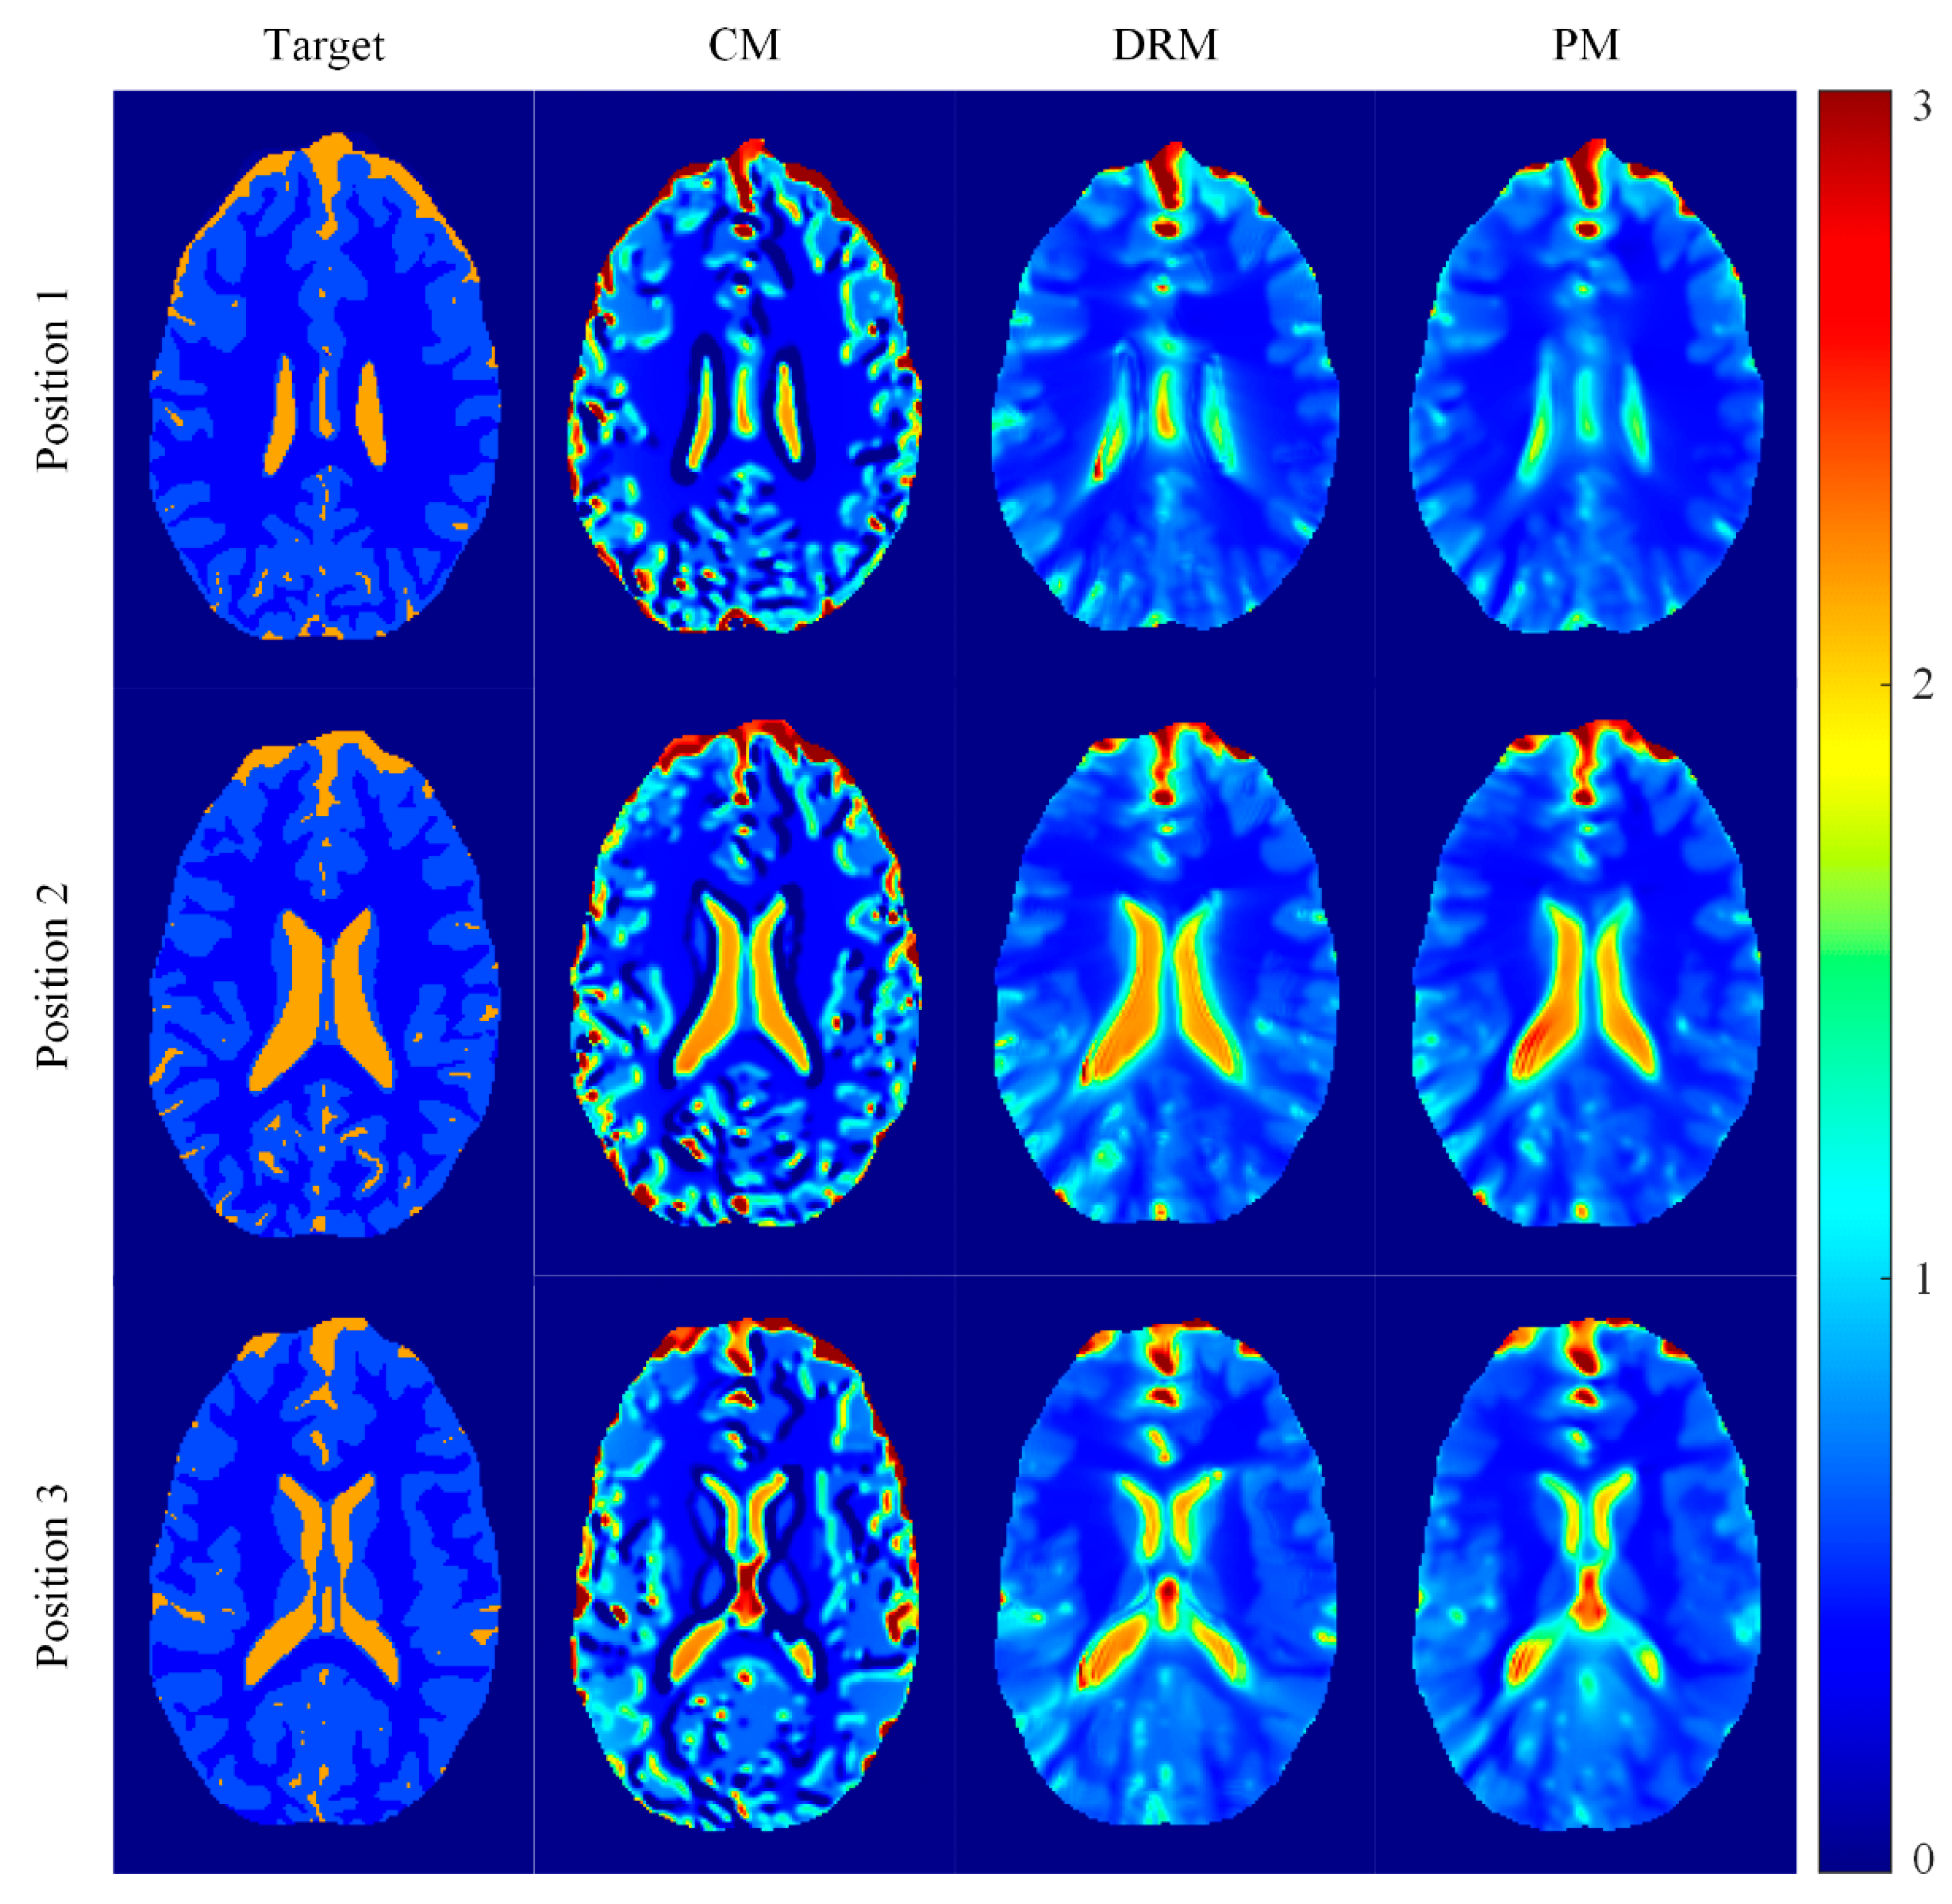

4.1. Phantom Simulation Results

4.2. Ella Head Simulation Results

| Measured | Conventional Method | Double Regularizations Method | Proposed Method | |

|---|---|---|---|---|

| Region 1 | 0.97 | 0.71 ± 0.31 | 0.84 ± 0.13 | 0.92 ± 0.08 |

| Region 2 | 2.01 | 1.56 ± 0.59 | 1.92 ± 0.25 | 1.98 ± 0.19 |